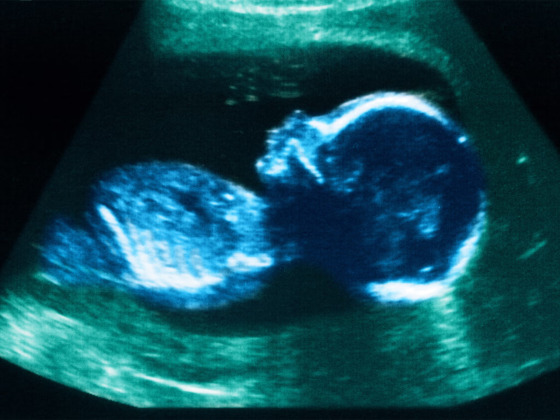

Această măsură ar duce probabil la punerea în pericol a vieții mult mai multor femei din cauza riscurilor pe care le implică avorturile tardive „DIY” (do–it-yourself / fă-o tu însuți) și, de asemenea, ar duce în mod tragic la creșterea numărului de copii viabili a căror viață este curmată cu mult peste termenul limită de avort de 24 de săptămâni și dincolo de momentul în care aceștia ar putea supraviețui în afara uterului.

Această modificare a legii ar duce probabil la punerea în pericol a vieții mult mai multor femei din cauza riscurilor pe care le implică avorturile tardive autoadministrate și, de asemenea, ar duce în mod tragic la creșterea numărului de vieți ale bebelușilor viabili la care se pune capăt cu mult peste termenul limită de avort de 24 de săptămâni și peste punctul în care aceștia ar putea supraviețui în afara uterului.